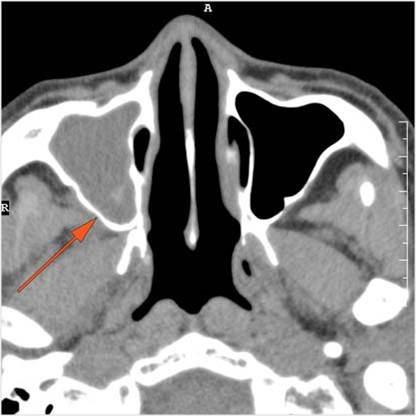

There is generalized mucoperiosteal thickening in the nasal cavity.

There is focal area of mucoperiosteal thickening or a destructive, ulcerative or necrotic abnormality of the nasal septum, turbinates or lateral walls of the nasal cavity.

There is infiltration in the posterior nasal cavity or sphenoethmoidal recess that is near to or protruding into the sphenopalatine foramen and pterygopalatine fossa.

There is evidence of bone erosion along the face of the sphenoid bone or pterygoid base or processes.